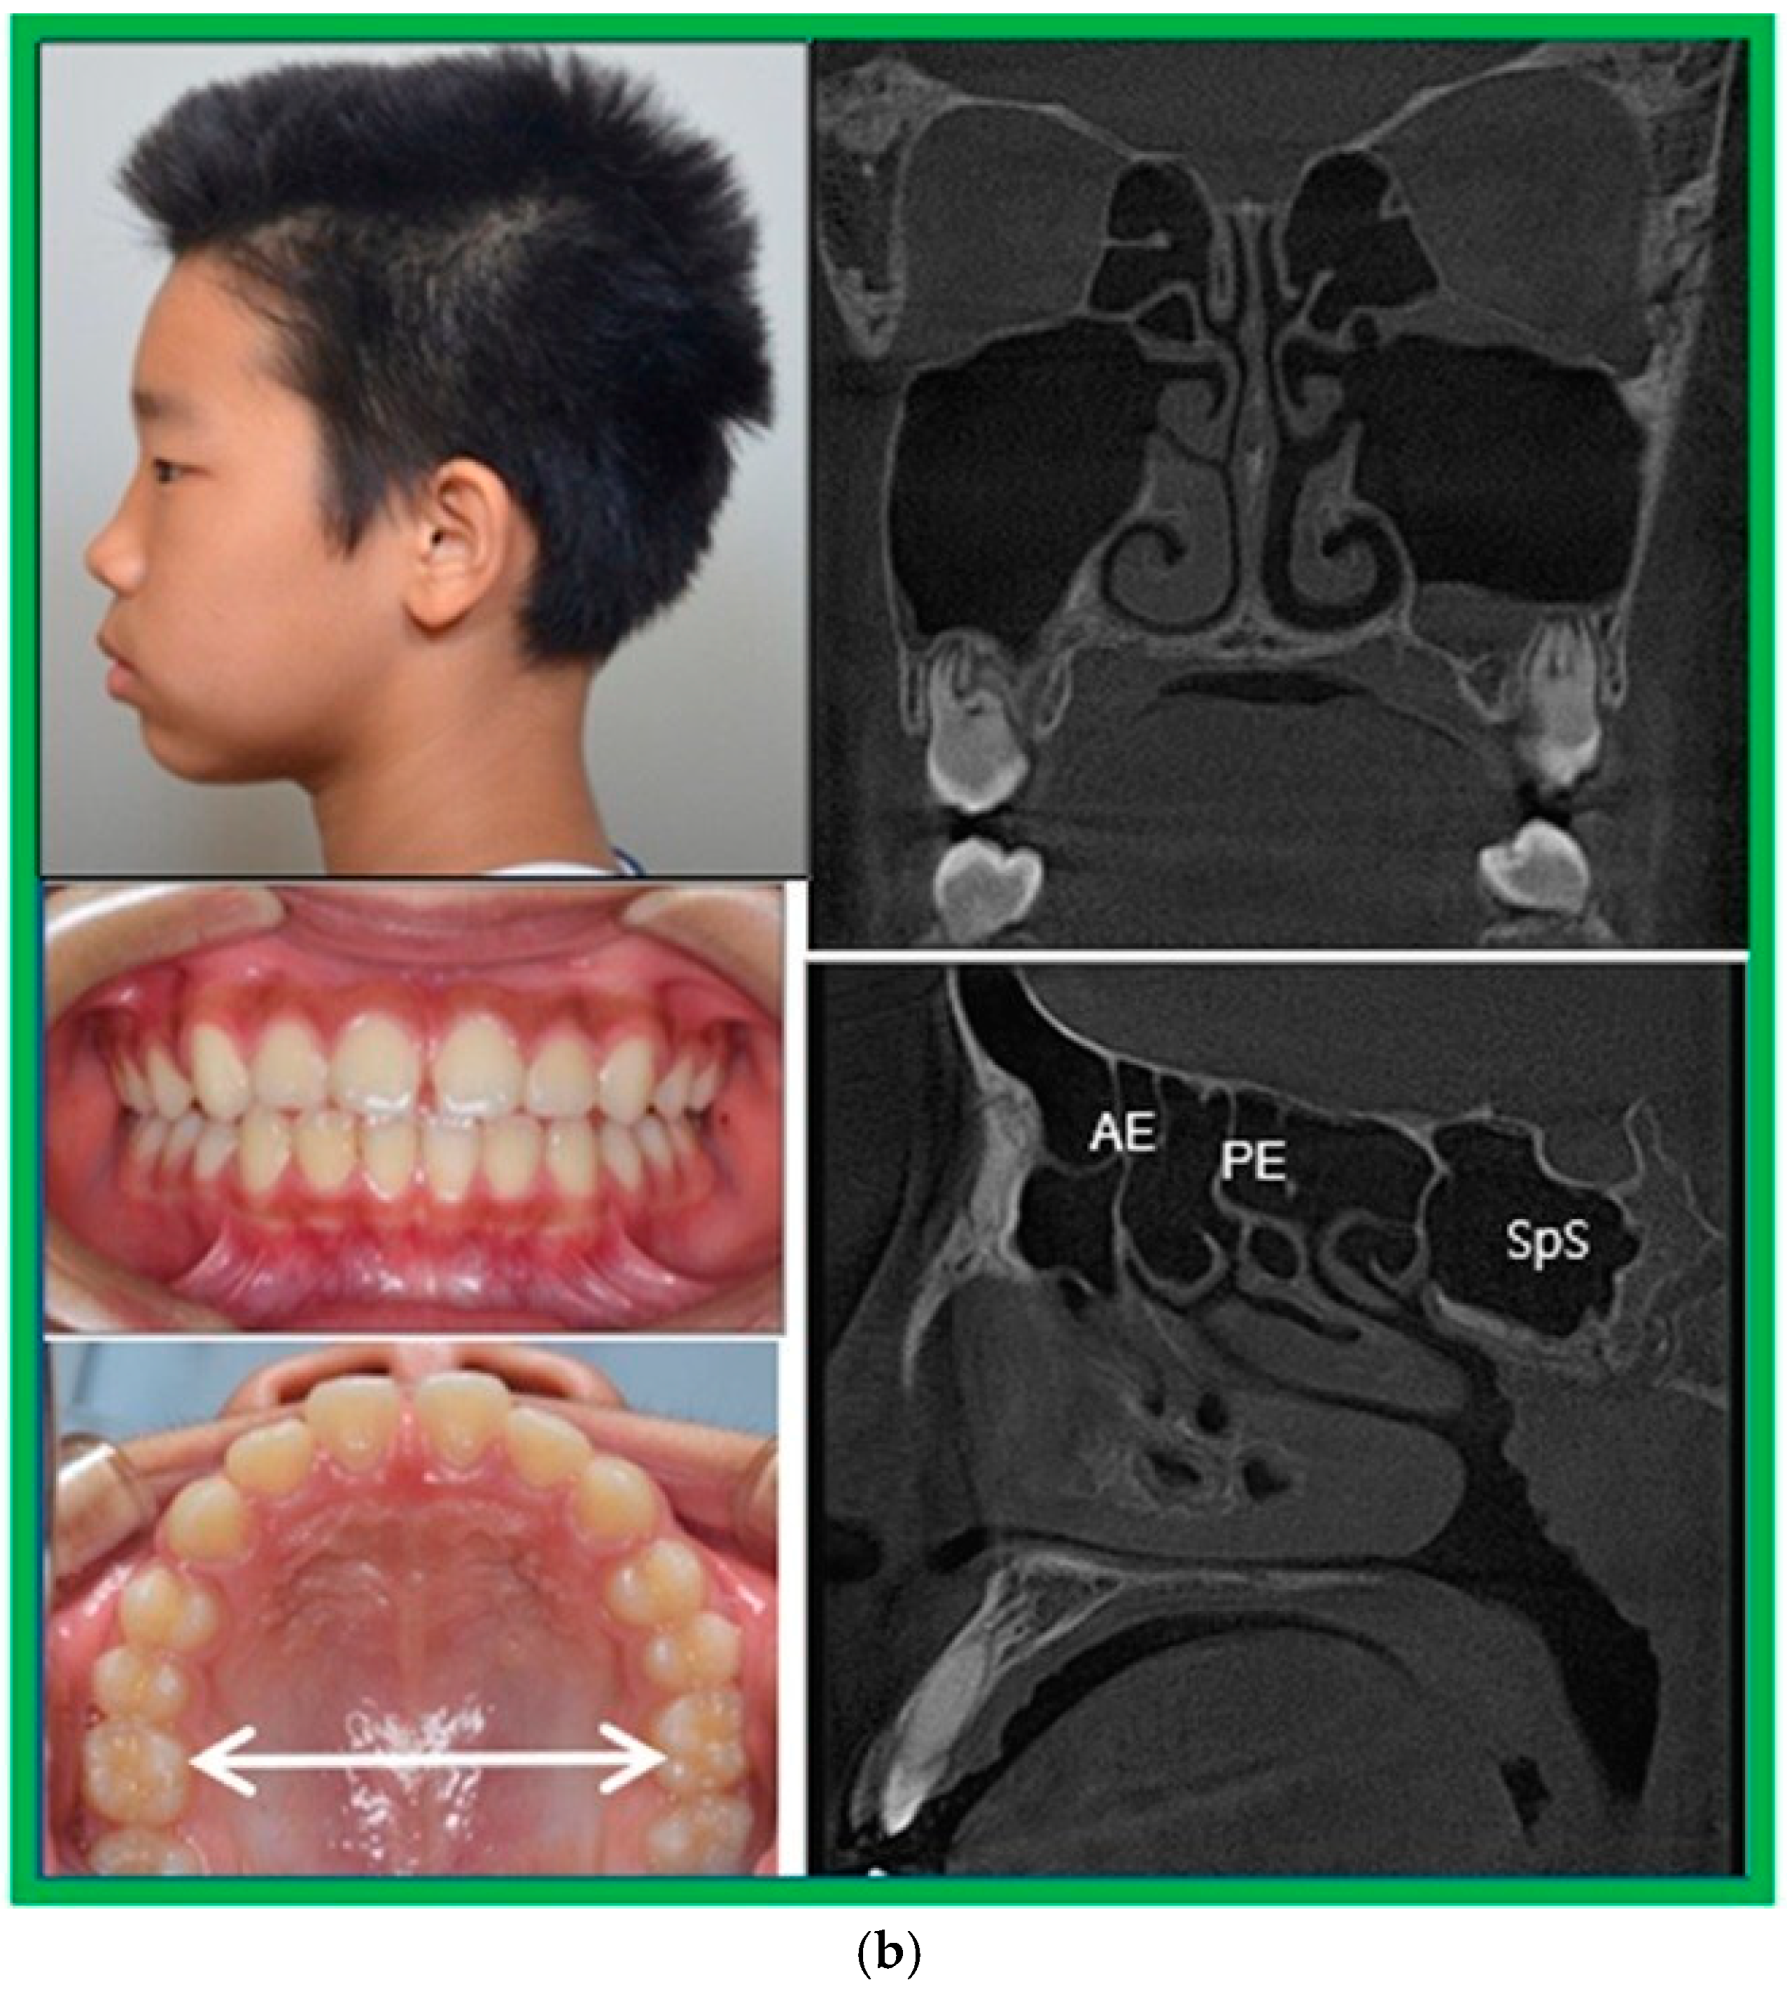

3.3. Patient Case Report